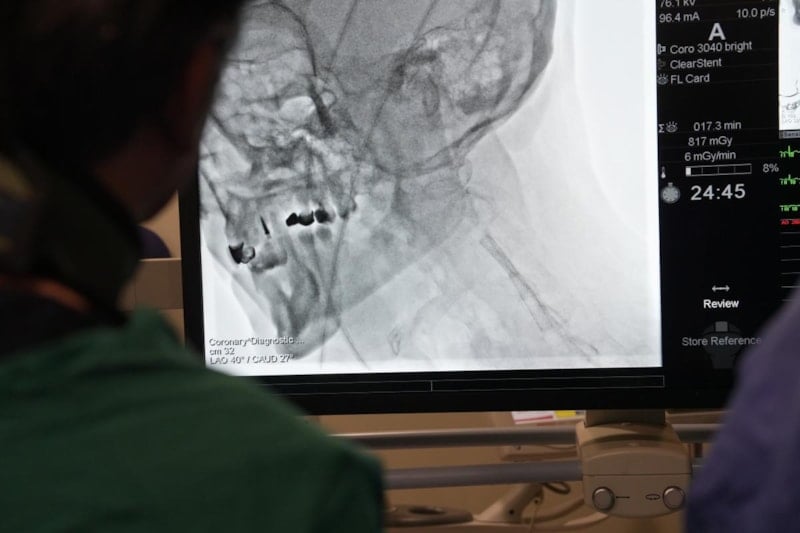

Medipol Acıbadem Bölge Hastanesi’nde, Kardiyoloji Uzmanı Prof. Dr. Ertuğrul Okuyan’ın öncülüğünde; özellikle Mısır, Pakistan, Tunus ve Cezayir’den gelen doktorlara “İleri Stent Teknikleri” ve “Kronik Damar Açma” gibi devrim niteliğindeki teknikler hakkında uygulamalı eğitimler verildi.

Eğitimler sırasında teorik bilgilerin yanı sıra, canlı operasyonlarla betonlaşmış damarlar yeniden hayata döndürüldü.

Kardiyoloji Uzmanı Prof. Dr. Ertuğrul Okuyan, “Kardiyoloji alanında çok donanımlı merkezlerimiz var. Birçok işlemi, yurt dışındaki benzerlerinden hiçbir fark olmaksızın gerçekleştiriyoruz. Bu, ülkemizin başarısıdır. Nitelikli hekimlerimizle birlikte Türkiye, sağlık turizminin yanı sıra sağlık eğitiminde de öncü bir konuma geldi. Deneyim ve tecrübelerimizi yurt dışındaki meslektaşlarımıza anlatmaya başladık. Hastanemizde de yurt dışından gelen meslektaşlarımıza geniş kapsamlı eğitimler veriyoruz. Bugün de kompleks koroner girişimler ve CTO kursumuzu gerçekleştiriyoruz.” dedi.

Teknolojinin gelişmesi ve hekimlerimizin denetimleriyle birlikte, eskiden açık cerrahiyle yapılan işlemleri artık kapalı yöntemlerle yapabildiklerini ifade eden Prof. Dr. Okuyan, “Kireçli ya da tıkalı damarlarda stent ve balon işlemlerini uyguluyoruz. Başarılı sonuçlar da alıyoruz. Ayrıca damar içi taş kırma işlemleri de yapıyoruz. Bu yöntemler, zor hastaları tedavi etmemize olanak sağlıyor. Yurt dışından gelen çok değerli meslektaşlarımıza bu konularda teorik ve pratik eğitimler veriyoruz. Bilgi ve donanımımızı meslektaşlarımıza aktarma imkânı buluyoruz.” şeklinde konuştu.

Yapılan açıklamanın ardından canlı cerrahi operasyonlara geçildi. Prof. Dr. Okuyan, Pakistan, Tunus, Cezair ve Mısır’dan gelen doktorlara cerrahi işlemleri adım adım anlatma imkânı buldu.